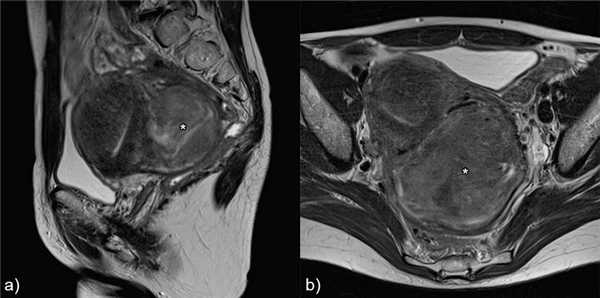

а) Аденомиома и лейомиома

Основной дифференциальный диагноз с лейомиомой.б) Изолированная/ювенильная кистозная аденомиома и accessory cavitated uterine mass - ACUM (термин не имеет адаптированного перевода на русский язык)

Рис.13 Аденомиома: а) сагиттальный Т2 и b) аксиальный Т2-взвешенные изображения, неоднородная гипоинтенсивная на T2 масса с плохо определенными границами, мелкими гиперинтенсивными фокусами в структуре (белые стрелки).

![]()

Рис.14 Лейомиома: а) сагиттальный Т2 и b) аксиальный Т2-взвешенные изображения, неоднородная гипоинтенсивная на T2 масса с четко определенными границами, масс-эффектом на окружающие ткани (звездочка). Есть также особенности, наводящие на мысль о аденомиозе.

Рис.15 Наружный аденомиоз: корональные T2 взвешенные изображения, субсерозная плохо отграниченная масса с низкой интенсивностью сигнала, мелкими гиперинтенсивными фокусами в структуре в левой стенке матки (белая стрелка), имитирующая эндометриоз. Также видны лейомиомы (звездочки).